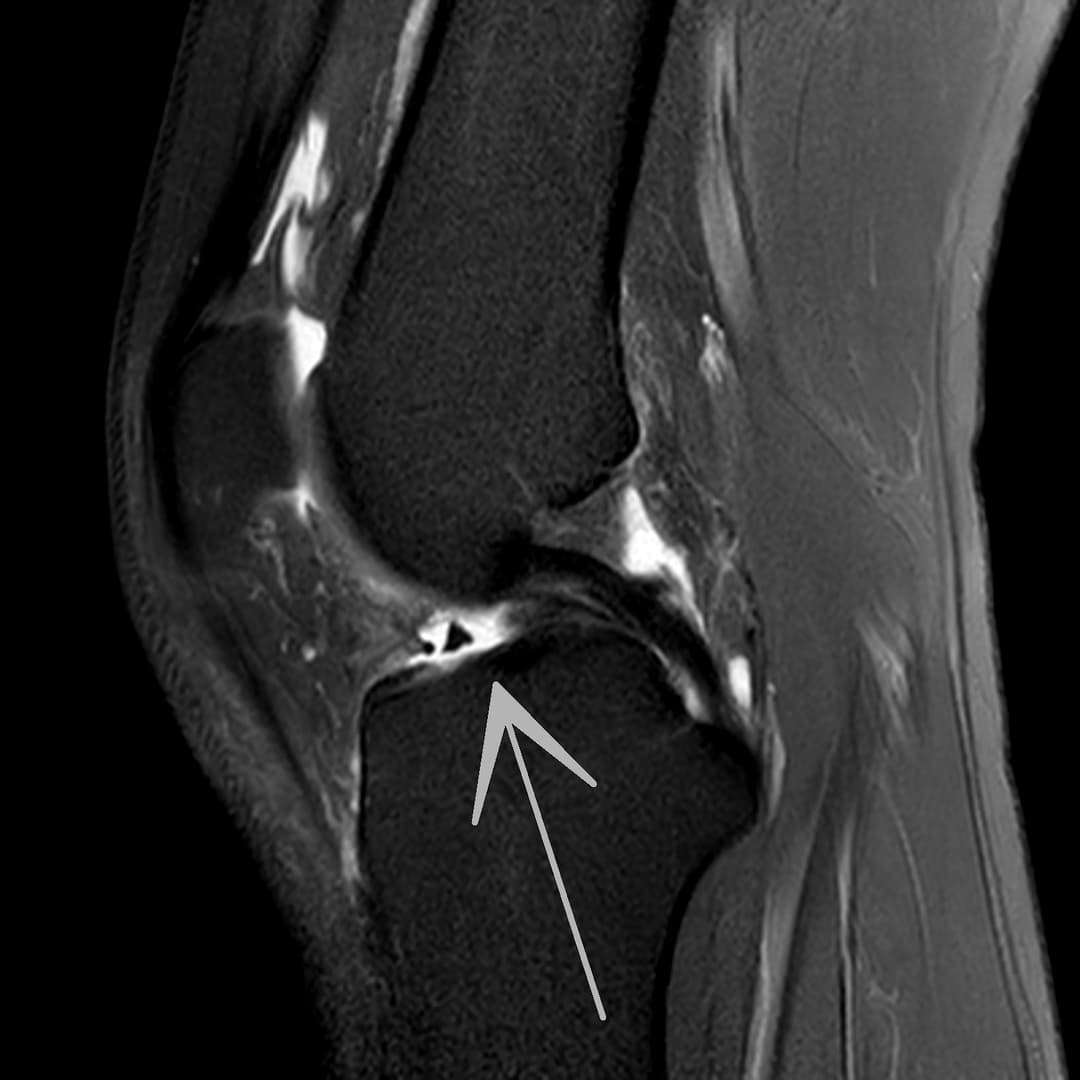

Fissure de grade 3 du segment moyen du ménisque médial.

Languette méniscale rattachée à la corne antérieure du ménisque médial avec aspect flottant sur le versant antérieur de l'échancrure.